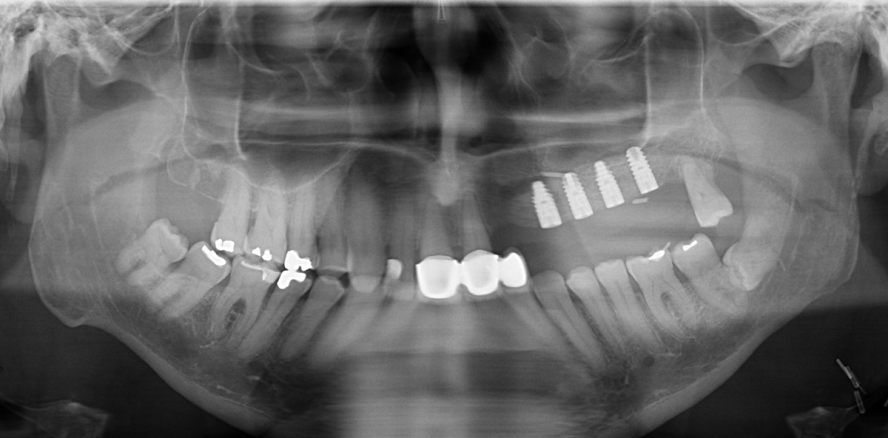

Die postoperativen Kontrolluntersuchungen zeigten zunächst einen regelgerechten Heilungsverlauf. In der Sprechstunde im August 2014 berichtete der Patient jedoch über eine zunehmende Einschränkung der Mundöffnung. Der klinische Befund ergab eine Schneidekantendistanz (SKD) von ca. 1 cm. Es zeigte sich ein stabiles und gut durchblutetes Transplantat (Abb. 2). Zur bildgebenden Diagnostik wurde bei dem Patienten zunächst ein Orthopantomogramm (Planmeca ProOne, Helsinki, Finnland) angefertigt (Abb. 3). In dieser zeigte sich intermaxillär links eine längliche, unscharf begrenzte Verschattung, die vom linken Kieferwinkel bis zum Fibulatransplantat im Oberkiefer reichte.

Postoperativ konnte durch die Abtragung der Ossifizierung eine deutliche Verbesserung der Mundöffnung erreicht werden. Zehn Tage postoperativ zeigte der Patient eine Schneidekantendistanz von 2,5 cm. Der Patient wurde angehalten, mittels Spatelübungen und dem TheraBite® Gerät die Mundöffnung täglich mehrmals zu trainieren. Bei der Kontrolluntersuchung im August 2015 weist der Patient eine Mundöffnung mit einer Schneidekantendistanz von 3,4 cm auf (Abb. 9). Das Orthopantomogramm (SCANORA 3D, SOREDEX, Tuusula, Finnland) zeigt keinen Hinweis auf eine erneute Verknöcherung des Gefäßstieles. Durch die verbesserte Mundöffnung konnten dem Patienten im August 2015 vier Implantate im linken Oberkiefer inseriert werden (Abb. 10).